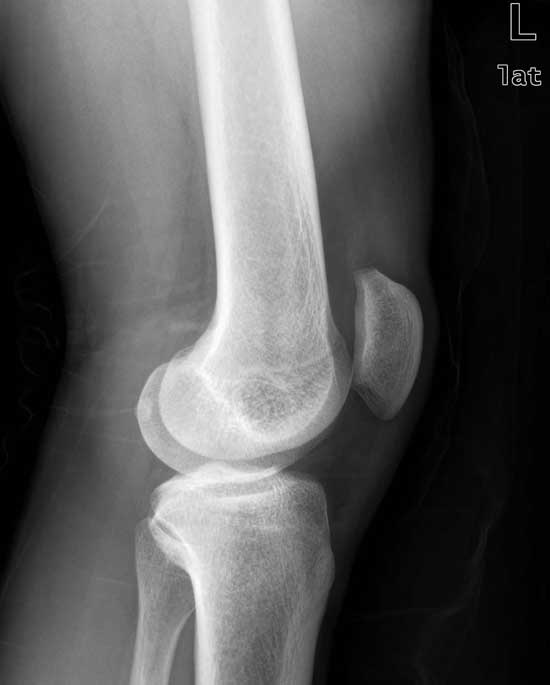

到院检查后发现,薛女士四肢关节压痛明显,双膝关节异常红肿,超敏C反应蛋白高达97.5mg/L,诊断为风湿性关节炎中期。规范化治疗三个疗程后,关节疼痛肿胀消失,行动关节活动无声响,未见关节麻木现象,膝关节能够自由屈伸、下蹲、行走。超敏C反应蛋白降至4.3mg/L,类风湿因子18.5IU/ml,临床诊断风湿病症消除恢复健康。

(图:患者治疗后左膝关节X线片)